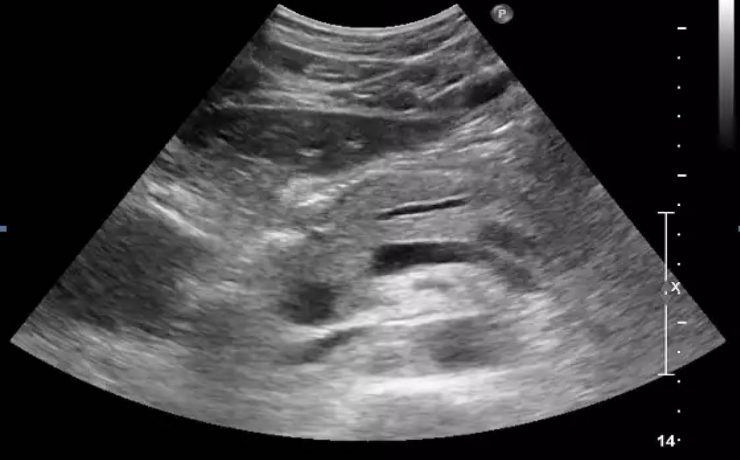

Patologías benignas de la próstata: prostatitis e hiperplasia benigna

En este estudio se llevó a cabo un análisis de la anatomía prostática; los factores más relevantes que regulan el crecimiento prostático y y las funciones de la glándula que podrían influir en la etiología de diferentes patologías de la próstata; parámetros claves en el diagnóstico temprano y de estas